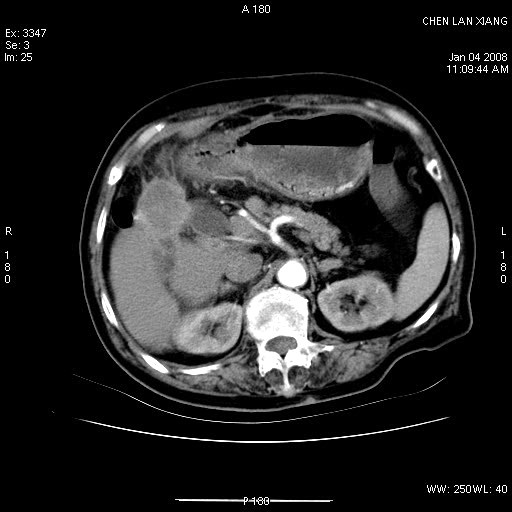

女,76岁,腹痛3-4天,b超示:肝内实性肿物,胆囊强回声,胆总管扩张.

考虑:1、胆总管下端结石伴梗阻性肝内外胆管扩张(肝左叶外侧段肝内胆管多发结石、胆管炎);

2、肿囊癌累及肝,不除外 黄色肉芽肿性胆囊炎。

1 胆总管末端结石伴肝内胆管结石,肝内外胆管扩张。2 胆囊扩大,胆囊壁不规则增厚,内见软组织密度影。考虑:慢性胆囊炎,不除外胆囊癌!

ct所见:1、 肝内胆管结石,肝内外胆管扩张。低位胆道梗阻,胆总管下端结石;2 胆囊扩大,胆囊壁不规则增厚

考虑:胆总管下端结石并肝内外胆管扩张,肝内胆管结石;

慢性胆囊炎

标题: 肝右叶病灶

胆囊癌侵犯肝右叶?

1)胆囊癌伴肝脏转移。2)胆总管下端结石、肝内胆管结石伴肝内外胆管扩张。